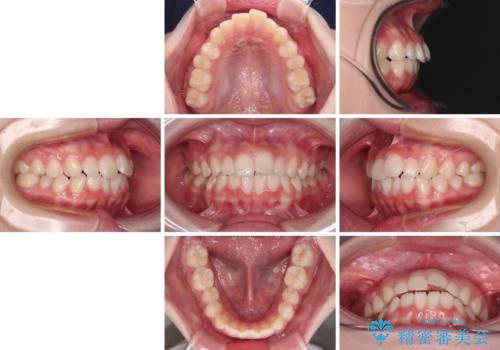

- 前歯のデコボコを気にして来院された高校生の患者様です。

捻れた前歯が前方に飛び出している点も気になっており、目立たない装置を希望されたため、インビザラインを用いて矯正治療を行うこととしました。

上下ともに少し捻れが残っていたため、治療の継続を提案しましたが、本人も親御さんも満足とのことで、治療を終えました。

捻れの改善により突出感も改善されました。